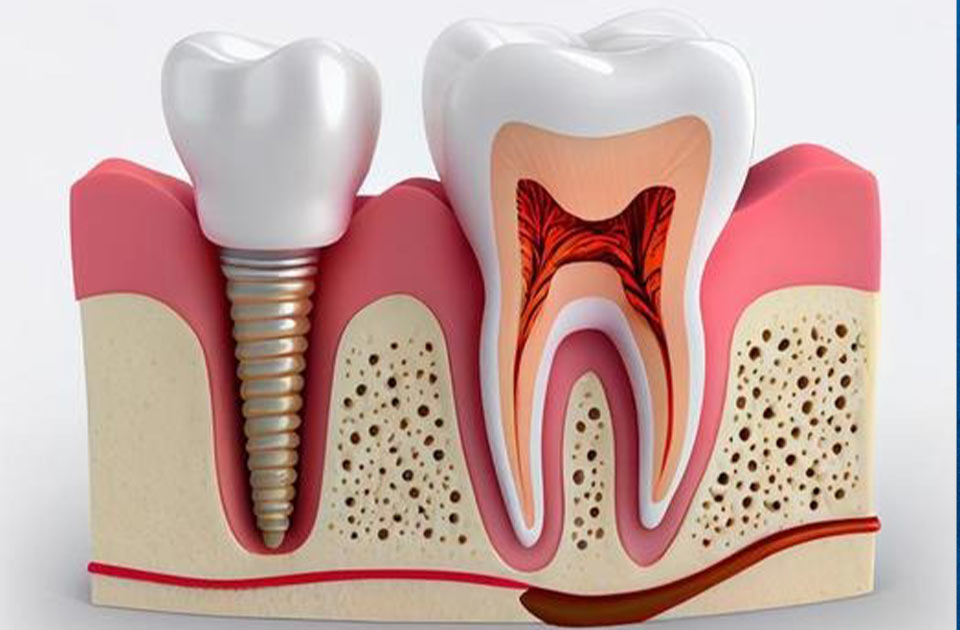

جراحی ایمپلنت دندان

احتمالا تا به الان با ایمپلنت دندان آشنا شده باشید با اسم آن به گوش شما خورده باشد ایمپلنت دندان یک جایگزین مناسب برای دندان های از دست رفته افراد می باشد .

این نوع از جراحی دندان همانند هر عمل جراحی دیگری کمی درد یا ناراحتی را به همراه دارد این عمل تحت بی حسی موضعی و یا آرامبخش انجام می شود تا در طول انجام جراحی فرد مورد نظر دچار هیچگونه دردی نباشد . در این جراحی یعنی جراحی ایمپلنت دندان ، دندانپزشک به شما جهت آماده شدن برای جراحی دستورالعمل هایی را می گوید که عبارتند از :

به طور کلی جراحی ایمپلنت دندان نیازمند تجربه کافی و مهارت بالایی می باشد .

البته باید توجه داشته باشید که قبل از ایمپلنت دندان باید چک بکنید که استخوان فک شما می تواند ایمپلنت دندان را نگه دارد و پس نزند و بعد به جراحی ایمپلنت دندان فکر کنید .